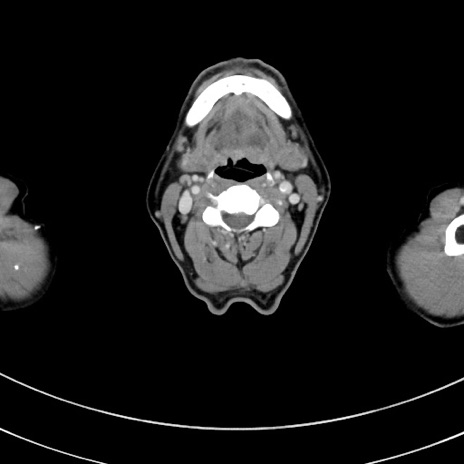

冠状断像